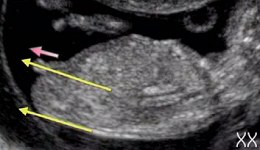

На таком сроке писи у них одинаковые.Срок 12-13 недель

Это мальчик

а это девочка

1. Анус 2. Губно-мошоночные бугорки 3. Ноги 4. Половой бугорок 7. Углубление уретры 8. Половые складочки

У мальчиков половой бугорок образует угол примерно 30 градусов или больше со спинкой.

У девочек половой бугорок образует угол меньше 30 градусов.